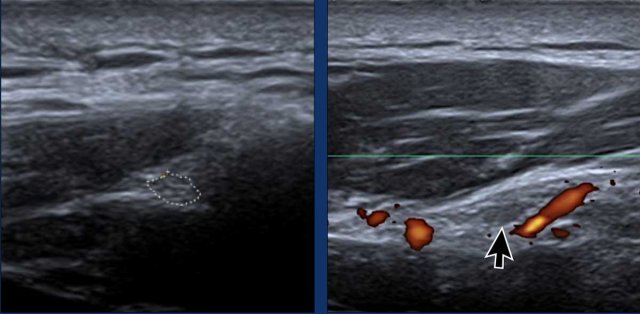

Spinoglenoid notch

Identify the scapular spine as a hyperechoic bony landmark.

Move the probe laterally until you locate the spinoglenoid notch, which is situated between the lateral scapular spine and the glenoid process.

The suprascapular nerve appears as a hypoechoic tubular structure with a fascicular pattern (arrow).

Power Doppler can be beneficial to trace the suprascapular vessels in order to find the nerve.

Examine for ganglion cysts, which may appear as hypoechoic, fluid-filled structures compressing the suprascapular nerve.

These cysts are often associated with tears of the posterosuperior glenoid labrum.